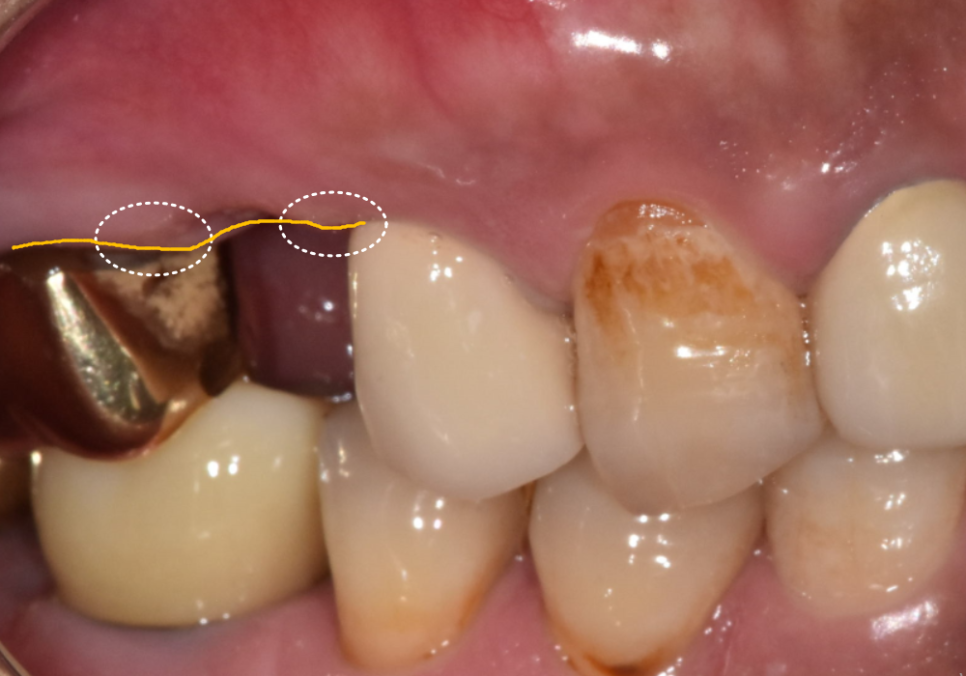

입안을 살펴보니

임플란트 바로 앞 치아(#35)가

많이 흔들리는 상황이었고,

잇몸도 부어있는 모습을 확인할 수 있었어요,